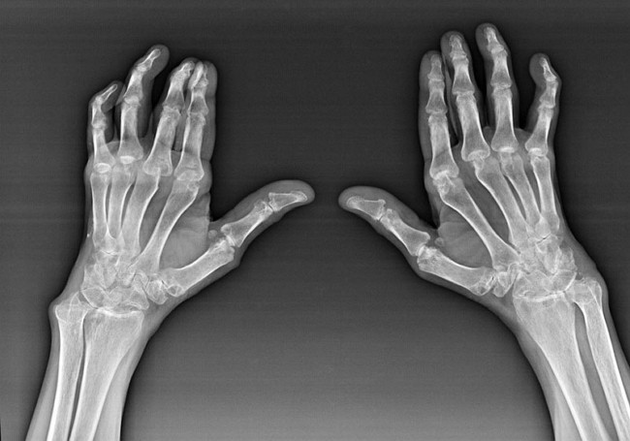

Artrite reumatoide

L'artrite reumatoide è una malattia in cui il sistema immunitario umano danneggia il tessuto del corpo. In altre parole, l'artrite reumatoide è un'autoimmunPatologia. Questa malattia è anche sistemica perché sono interessati molti tessuti ((((Muscoli, articolazioni, vasi, ecc.) e organi (Cuore, reni, polmoni, ecc.) nel corpo.

Nonostante il fatto che l'artrite reumatoide sia una malattia sistemica, le articolazioni soffrono in misura maggiore, mentre la lesione di altri tessuti e organi è sullo sfondo. Con questa malattia, possono essere influenzati quasi tutti i tipi di giunti a spazzole (Pareti del tutore, percorsi carpale, articolazioni metacarpali, interpalanx). La lesione è generalmente simmetrica (Questo. Le stesse connessioni sono interessate) Dolore in articolazioni danneggiate, accompagnato da gonfiore. Al mattino, mentre si alza dal letto, c'è una certa rigidità nelle articolazioni colpite, che durano circa 1 ora e possono quindi scomparire senza traccia.

Molto spesso con artrite reumatica vicino alle articolazioni interessate del pennello (Più spesso le articolazioni interfalanx piano-falange) Appaiono i reumatoidi. Sono una formazione arrotondata che è sotto la pelle. Queste formazioni sono più comuni sul retro sul pennello. Con la palpazione sono stretti, inattivi e indolore. Il numero di essi può variare.